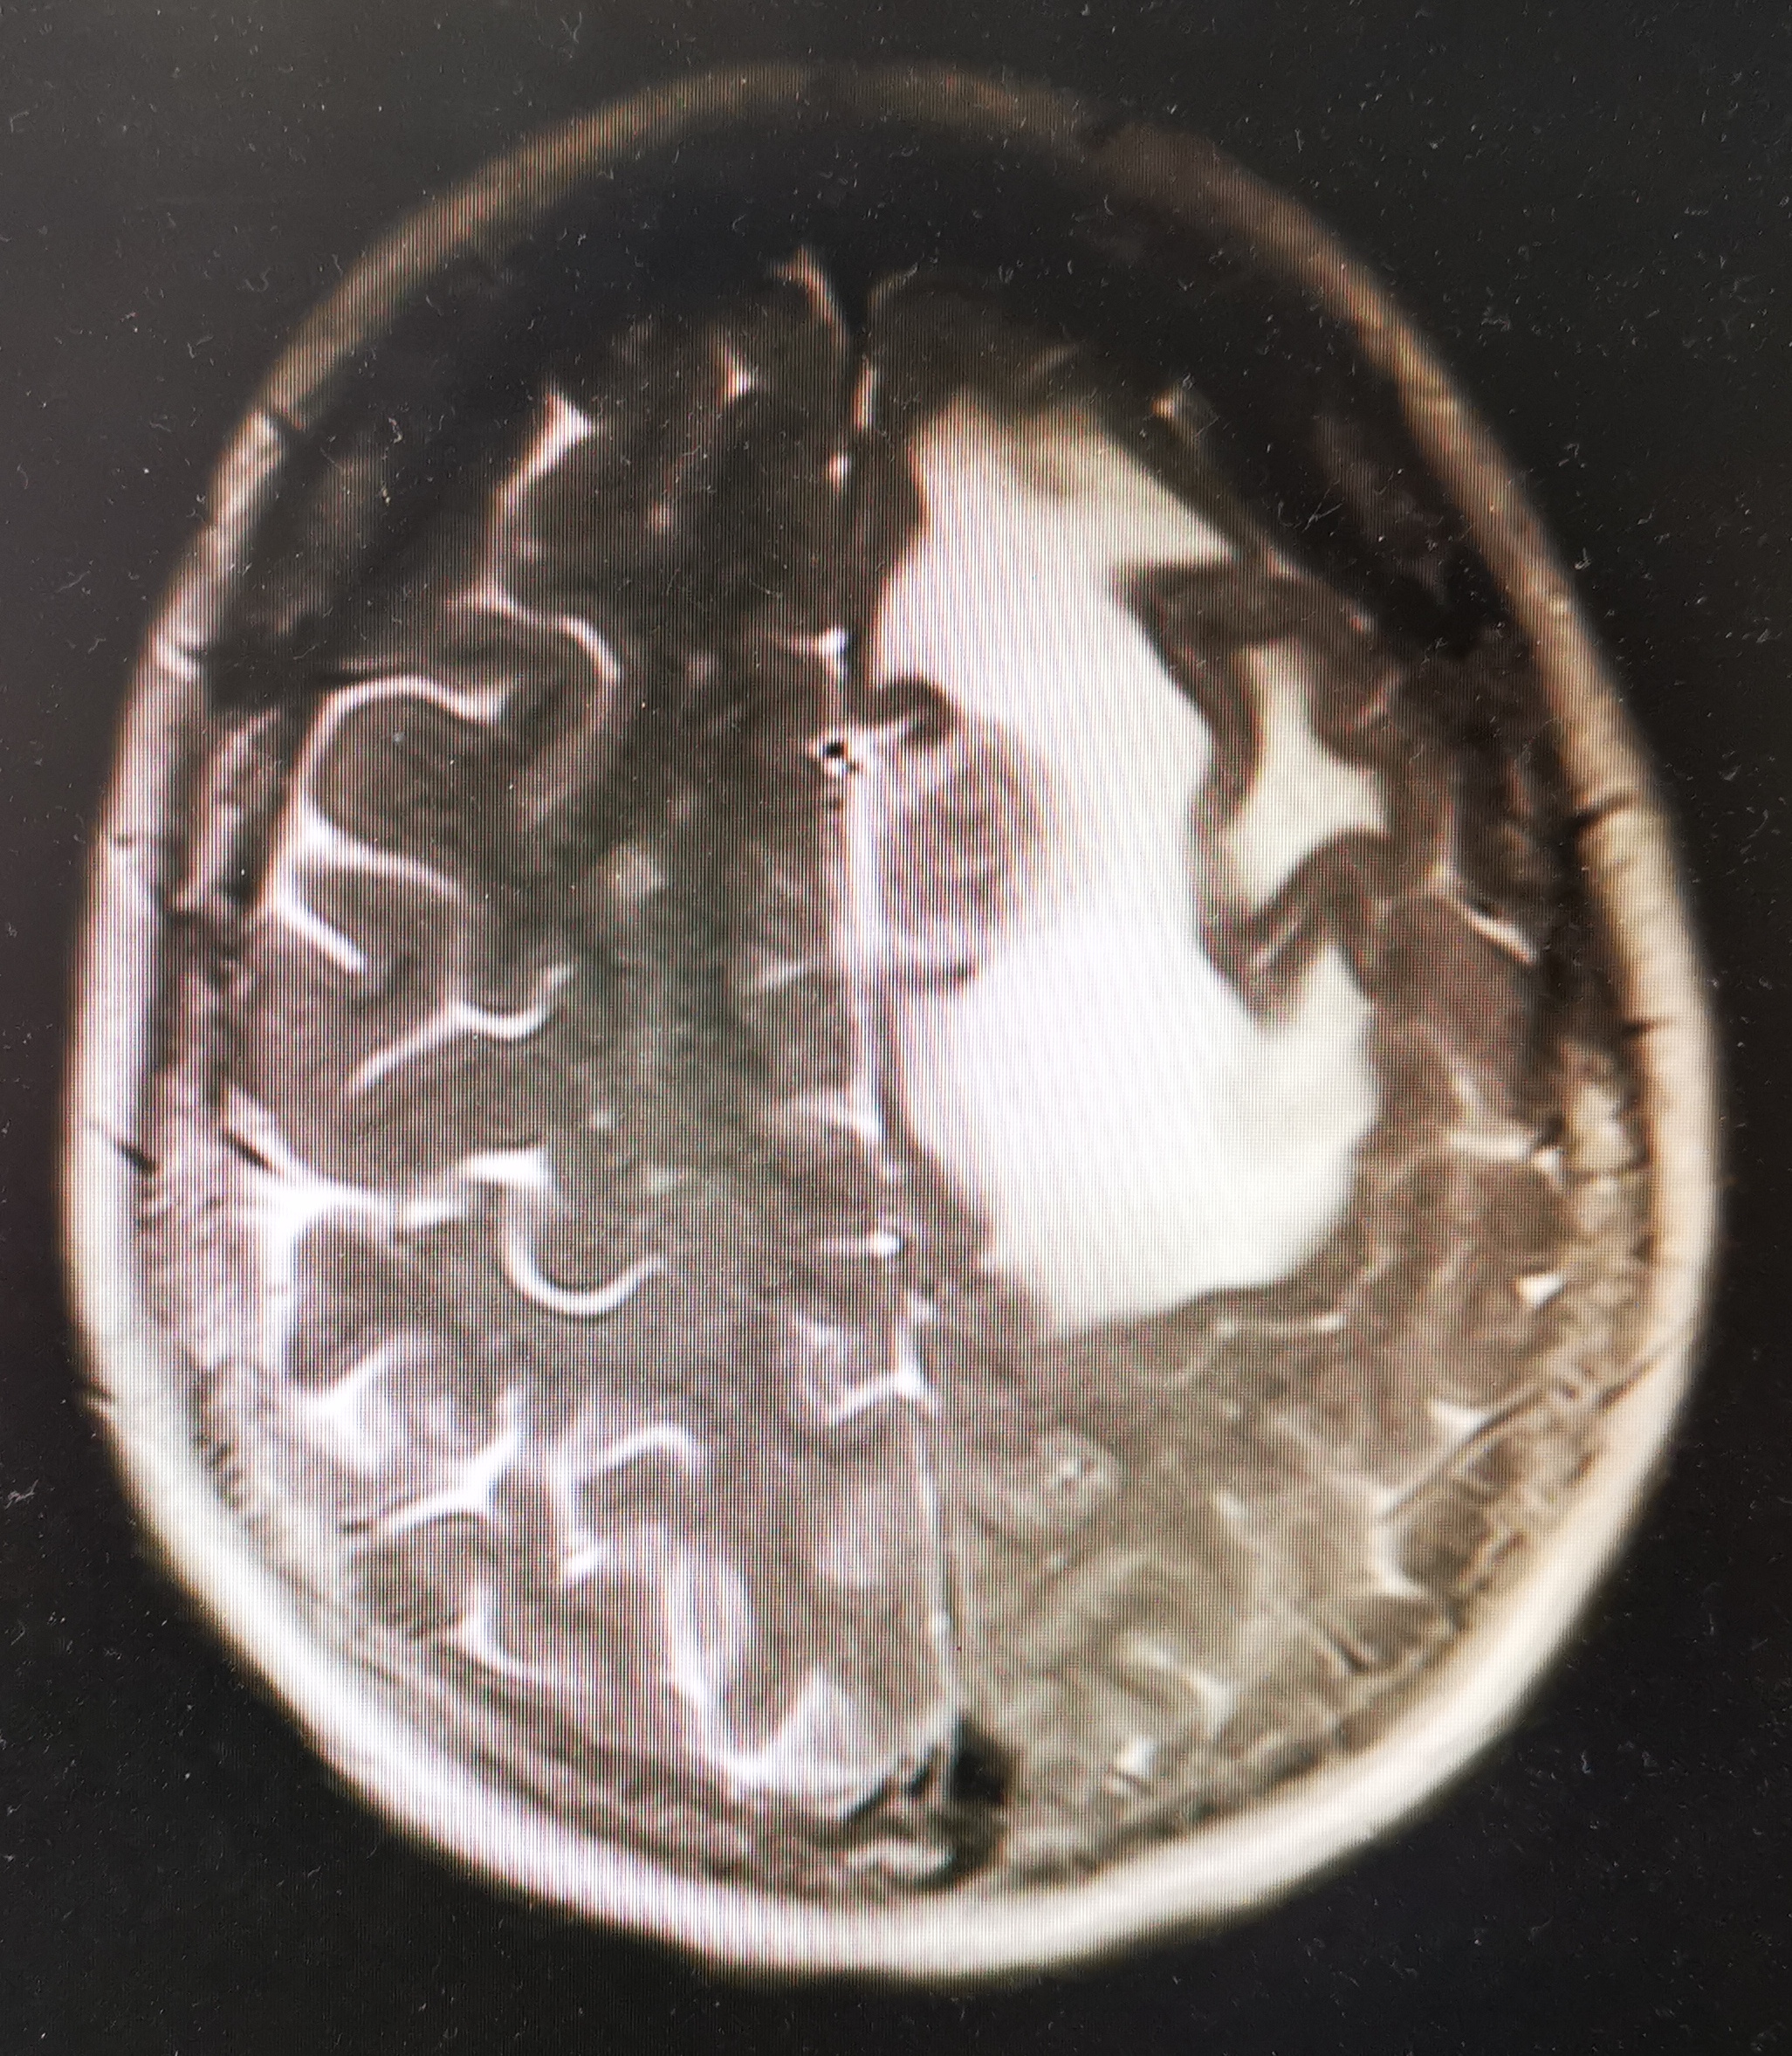

“不好,可能脑转移了!”我心里想到可能的恶果,一边安慰她一边很快给她开具了颅脑MRI,嘱咐尽快去检查,然后回来诊室找我。

一刻钟后她回来了,这时我已经打开了她的影像图片,很遗憾,电脑显示出现大面积异常信号区,很明确的转移了!看到她绝望的神情,以及伤心的哭泣声,我痛苦极了。

肺癌图片 脑转移图片

脑转移MRI图片

7. 肿瘤远处转移引起的症状。肺癌最常转移到中枢神经系统和骨,症状与转移部位功能相关。

回到文初,年轻的学生早早的出现转移,除了发现时病期较晚,没有规范治疗也是重要原因。